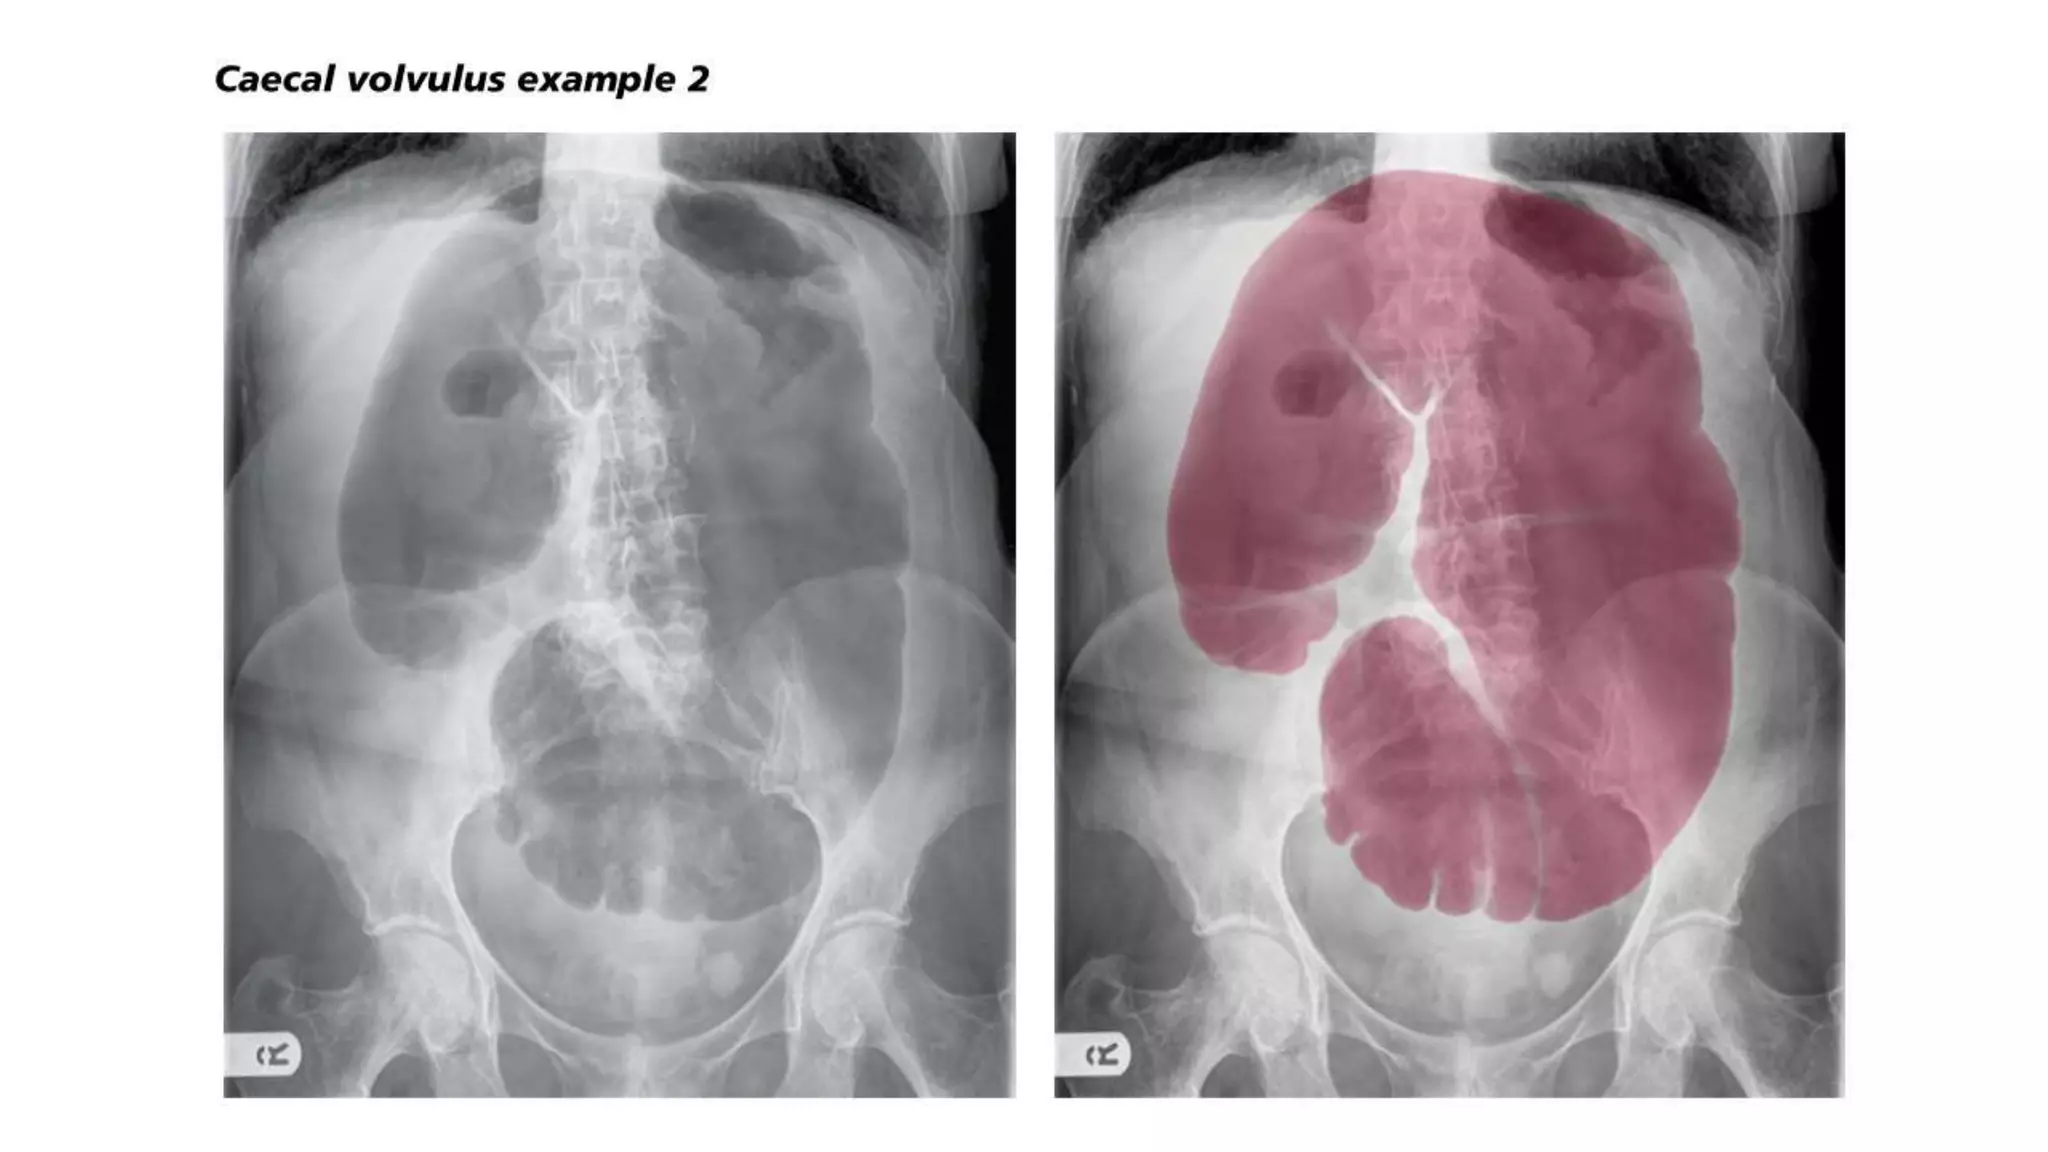

• CT scan — In patients with axial torsion of the cecum (type I or II), a

obstruction (a massively dilated cecum with associated small bowel

dilation) (image 5) or signs of colonic or small bowel ischemia (mural

thickening or mesenteric edema) [9]. In patients with a cecal bascule (type

III), CT scan shows the cecum folding upward, resulting in obstruction

without the axial twist of the mesentery (image 6).